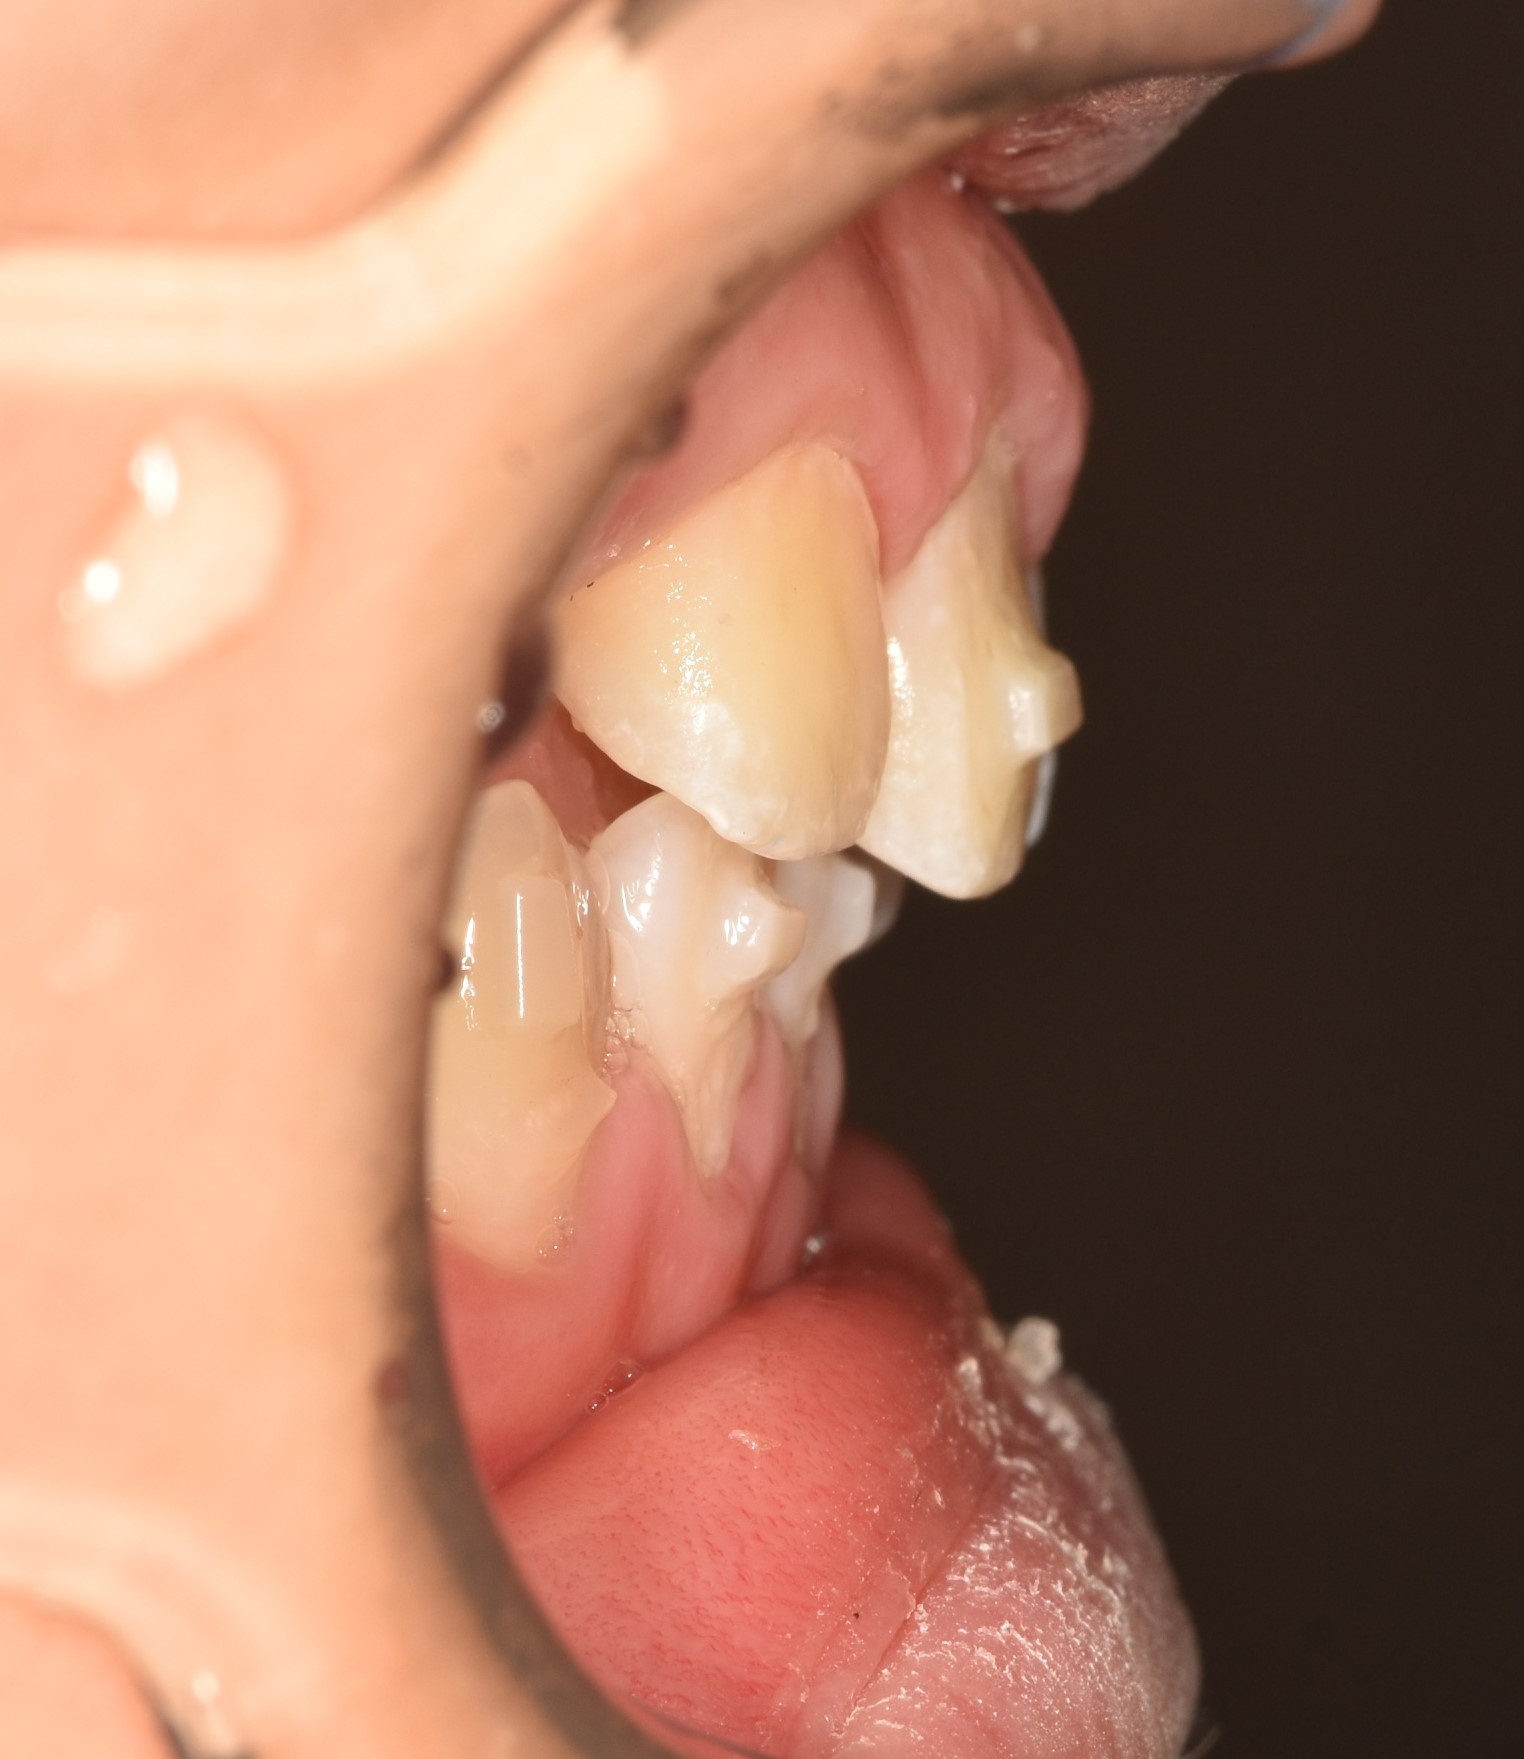

1년반의 투명교정이 끝나고 치아가 예쁘게 자리 잡았습니다.

아래쪽 새로 나오는 어금니가 뒤로 기울어져나네요. 맹출을 더 기다린뒤 자연적인 해소가 안되면 부분적으로 해결해주기로 하였습니다. 제가 교정을 해준 친구.. 끝까지 예쁘게 해줄거에요♥